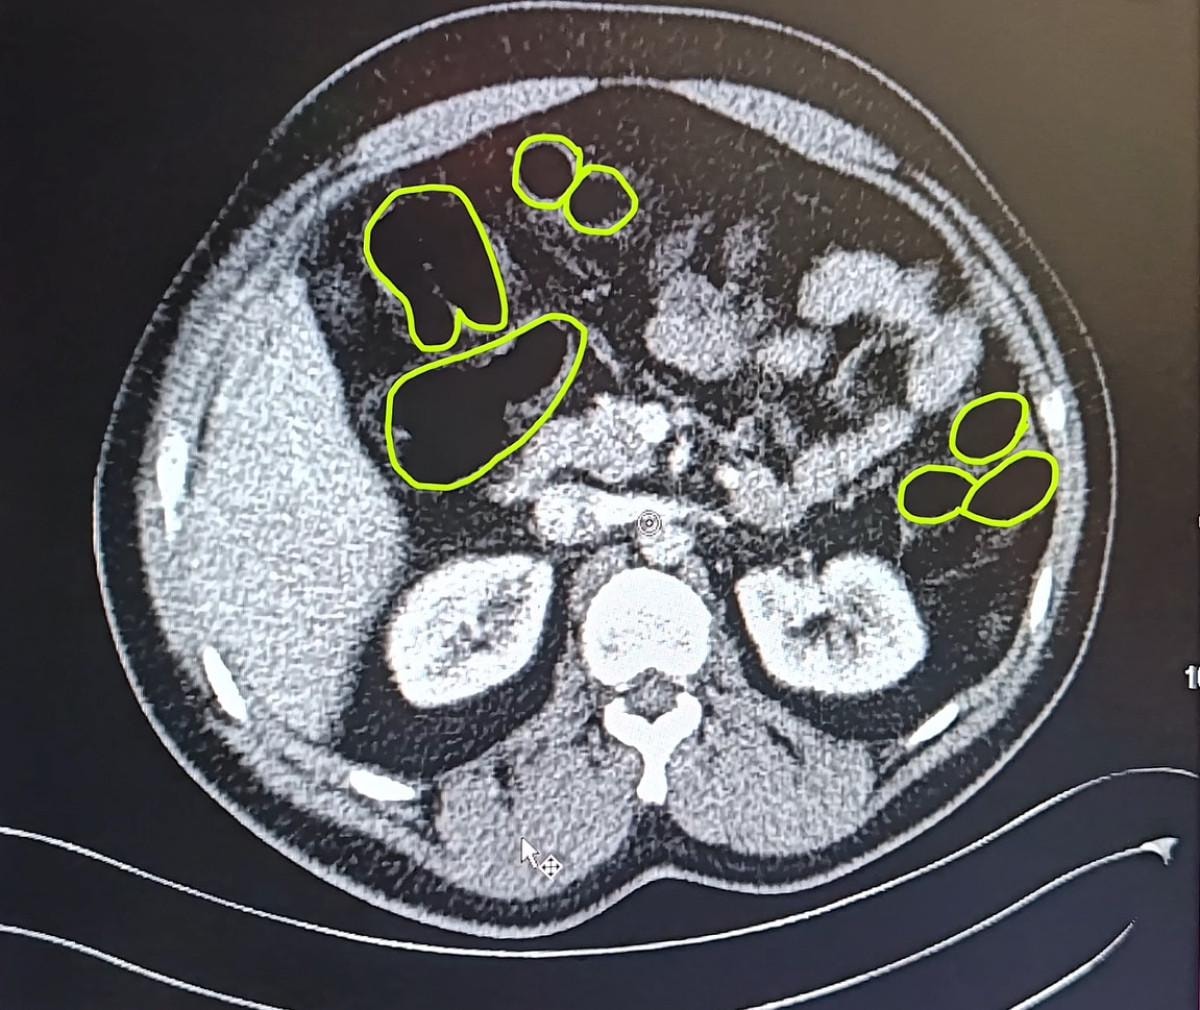

Zanlıların uyuşturucu maddeleri yutmuş olabileceğini değerlendiren ekipler bu kişileri hastaneye götürdü.

MİDELERİNDEN UYUŞTURUCU ÇIKTI

Röntgenlerinde midelerinde uyuşturucu madde olduğu belirlenen zanlılardan 20 gram çeşitli uyuşturucu madde ile 117 uyuşturucu hap ele geçirildi.